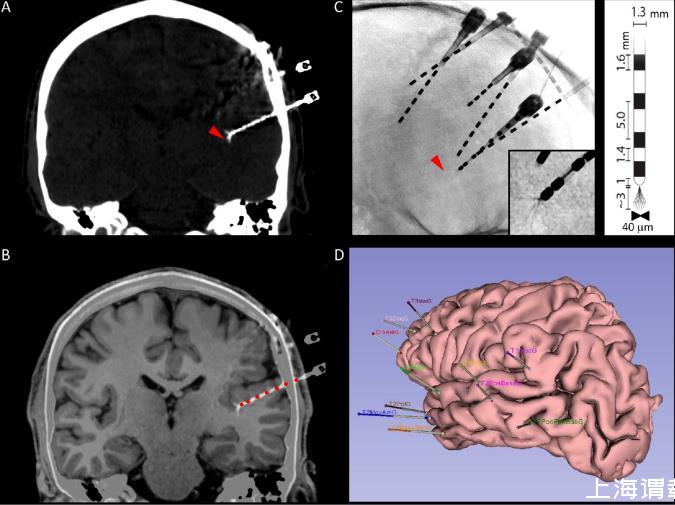

圖1.多模態微電極識別。A.冠狀面的顱骨計算機斷層掃描(CT),顯示了宏觀電極的軌跡以及微電極束的位置(紅色箭頭)。B.CT掃描與解剖學T1磁共振成像(MRI)的自動疊加,使得能夠可視化微電極在腦實質中的位置,同時還能自動識別沿腦內軌跡的宏觀電極接觸點(紅色圓圈)。C.放射影像顯示了腦內電極的二維位置。紅色箭頭指示了一個微電極束的位置,在前幾張中可見。插圖:微電極導線的放大圖。注意微導線的散開情況。右側插圖:宏觀-微電極幾何形狀的示意圖。D.受試者皮質解剖結構的三維Epiloc解剖重建,顯示了腦內宏觀電極的植入方案。

顱內電極的立體定向植入在神經外科進行。在將微電極插入專用的空心宏觀電極之前,神經外科醫生會將微導線剪至規劃期間確定的所需長度(通常為2-3毫米,補充圖1)。使用Yasargil顯微剪刀將它們全部剪成相同長度,并且垂直于電極軸,然后輕輕向外彎曲,直到它們形成像“傘”一樣的散開模式,當它們在腦內伸展時這種模式會保持(圖1)。這種散開模式提供了更好的記錄動作電位的機會。所有電極都用空心螺釘固定在顱骨上,以防止術后電極移動(錨定螺栓長度13毫米,以及LSBK1-AX-06,長度21毫米)。一旦所有顱內電極都植入后,用肥皂、水和聚維酮碘清潔并消毒患者的皮膚。然后對頭部進行處理,為長期視頻腦電圖記錄做準備,并仔細包扎(圖2和表1),這對于避免對電極造成任何損壞以及提高患者住院期間的舒適度是必要的。